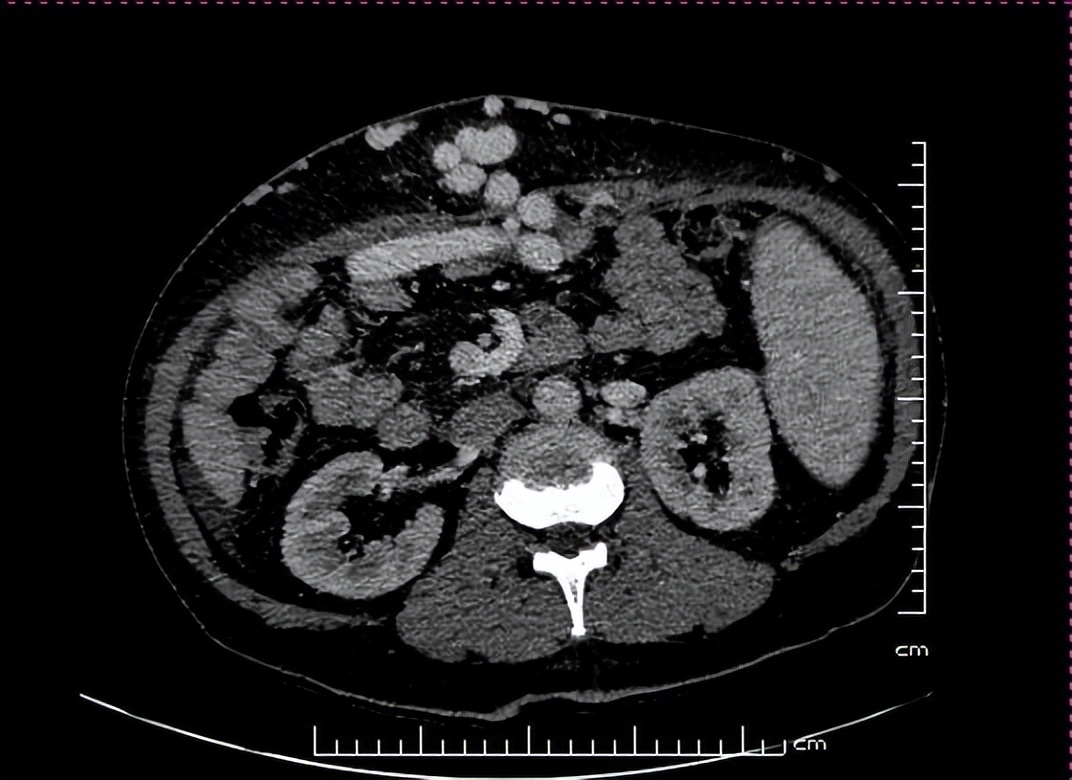

术前肝脏三期增强CT提示肝硬化